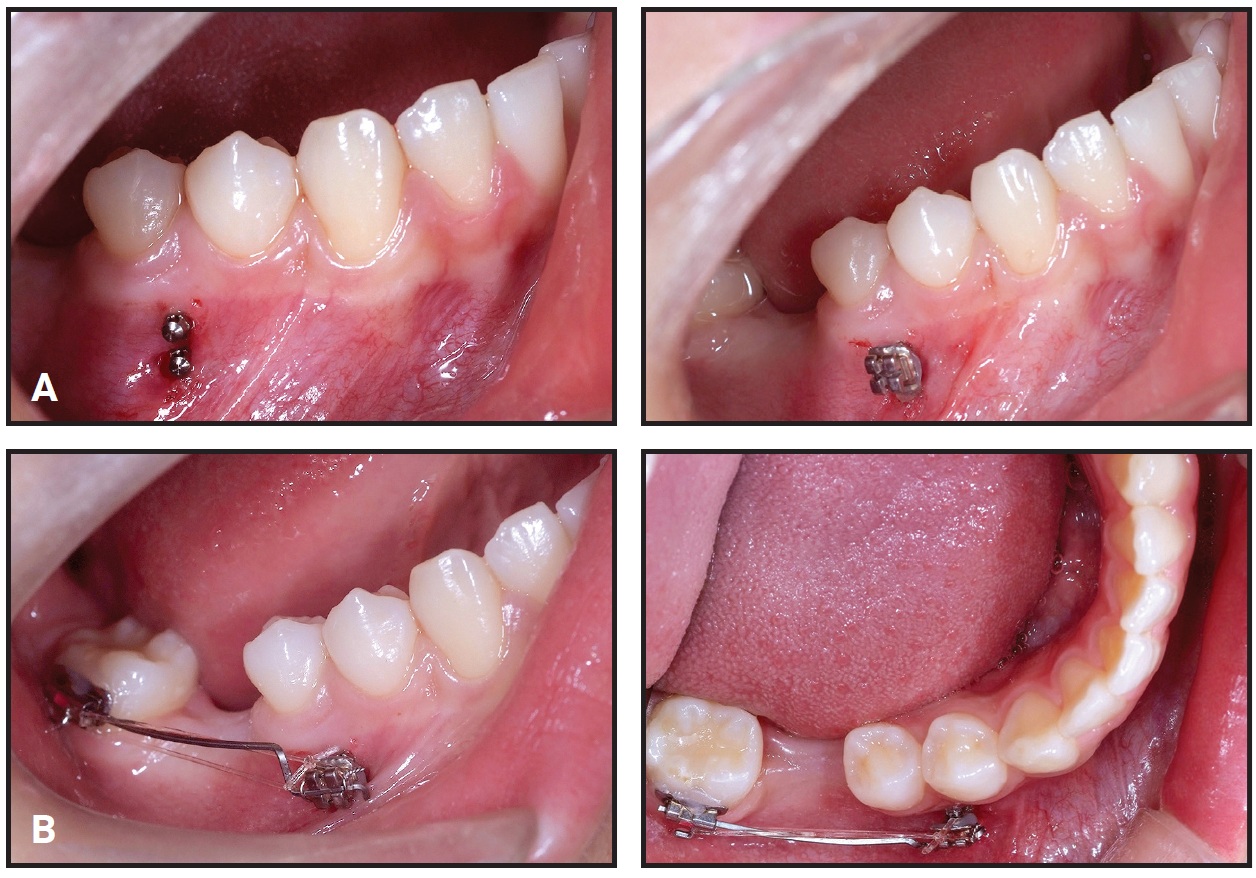

Two small-headed, 6mm micro-implants* were placed into the buccal alveolar bone between the lower left first and second premolars (Fig. 2A). The micro-implants were tied together with stainless steel ligature wire and built up with composite resin. A standard .018" upper-incisor bracket was bonded to the composite (Fig. 2B), a tube was bonded to the lower second molar, and an .017" × .025" TMA** sectional wire was inserted to connect the bracket and tube.

Fig. 2 Case 1. A. Two micro-implants* placed between lower left first and second premolars and built up with composite. B. Bracket bonded to composite and connected to second-molar tube with TMA** sectional wire.

After six weeks of treatment, two small-headed 6mm micro-implants were placed into the buccal alveolar bone between the lower right first and second premolars, tied with a stainless steel ligature wire, and built up with composite resin, as in Case 1 (Fig. 8). A standard .018" upper-incisor bracket was bonded to the composite, a tube was bonded to the lower second molar, and an .017" × .025" TMA sectional wire was inserted. Reactivation was performed by tightening the ligature wire every four weeks (Fig. 9).

Fig. 8 Case 2. A. Bracket bonded over two micro-implants between lower right first and second premolars, as in Case 1. B. Mesial force applied with TMA sectional wire.